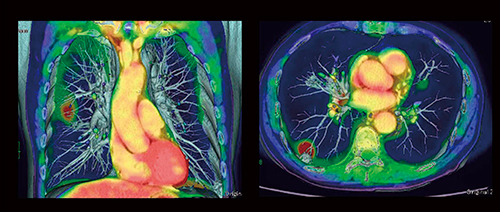

図11 肺腫瘍

PETと3D-CTAのフュージョン画像